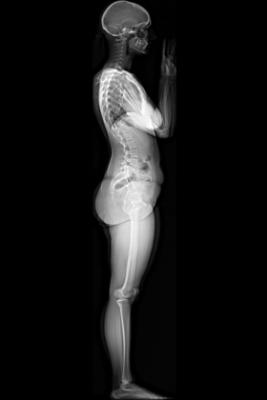

Image courtesy of EOS Imaging.

January 27, 2015 — EOS Imaging announced that the U.S. Food and Drug Administration (FDA) has cleared the Micro Dose feature of the EOS imaging system for pediatric imaging.

Micro Dose represents a breakthrough for patients with orthopedic conditions requiring frequent imaging exams for the continuous monitoring of disease progression and treatment. Initial results presented at the 2013 French Society of Radiology annual meeting (JFR 2013) and during the 2014 annual meeting of the Radiological Society of North America (RSNA 2014) concluded that Micro Dose generates dosage levels equivalent to a week of naturally-occurring background radiation in pediatric patients receiving 2-D and 3-D follow-up examinations.

Pediatric patients remain particularly sensitive to adverse effects associated with excessive exposure to radiation. Most notably, pediatric patients with scoliosis require frequent imaging sessions to monitor treatment progression, which can increase the risk of radiation-induced cancer later in life.